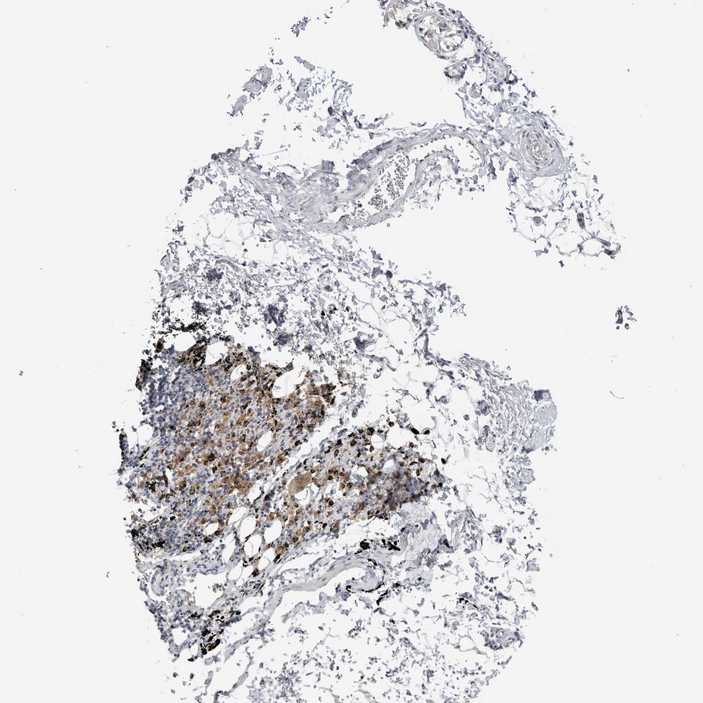

SOFT TISSUE 1 - Antibody stainingi

Antibody staining in the annotated cell types in the current human tissue is reported as not detected, low, medium, or high, based on conventional immunohistochemistry profiling in selected tissues. This score is based on the combination of the staining intensity and fraction of stained cells.

Each image is clickable and will lead to virtual microscopy that enables deeper exploration of all samples and also displays staining intensity scores, fraction scores and subcellular localization as well as patient and tissue information for each sample.

Antibody HPA024321

Fibroblasts Not detected

Peripheral nerve Not detected